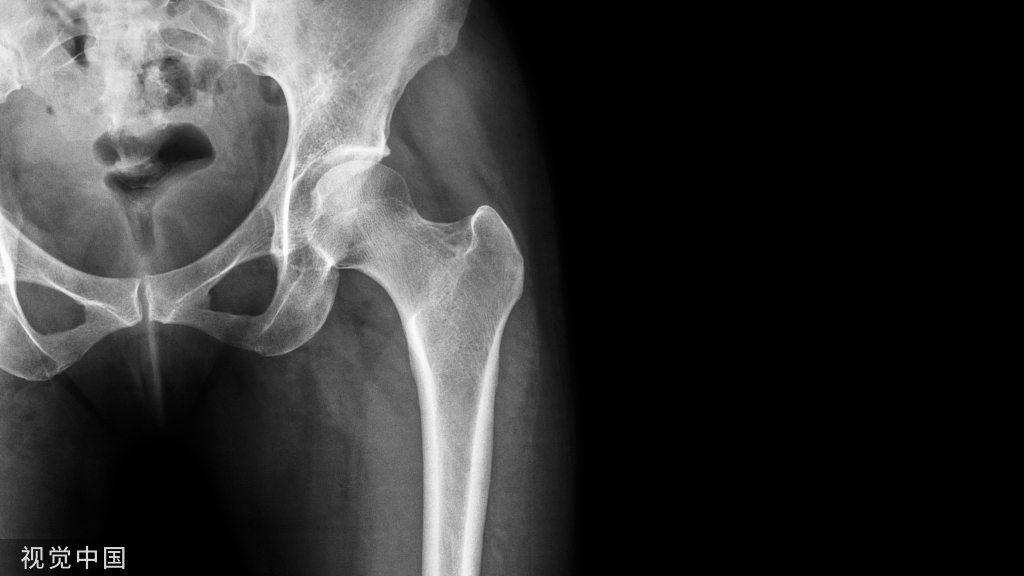

图5:A和B,一名57岁女性的左髋部X光片。A:无骨水泥全髋关节置换术后7年的正位X线片显示,由于聚乙烯磨损,股骨头关节偏心,大转子移位骨折并伴有溶骨性病变(箭头)。B:X线片,髋臼假体翻修8年后,用双张力带钢丝固定大粗隆并植入同种异体骨,显示大粗隆良好愈合和同种异体骨融合。